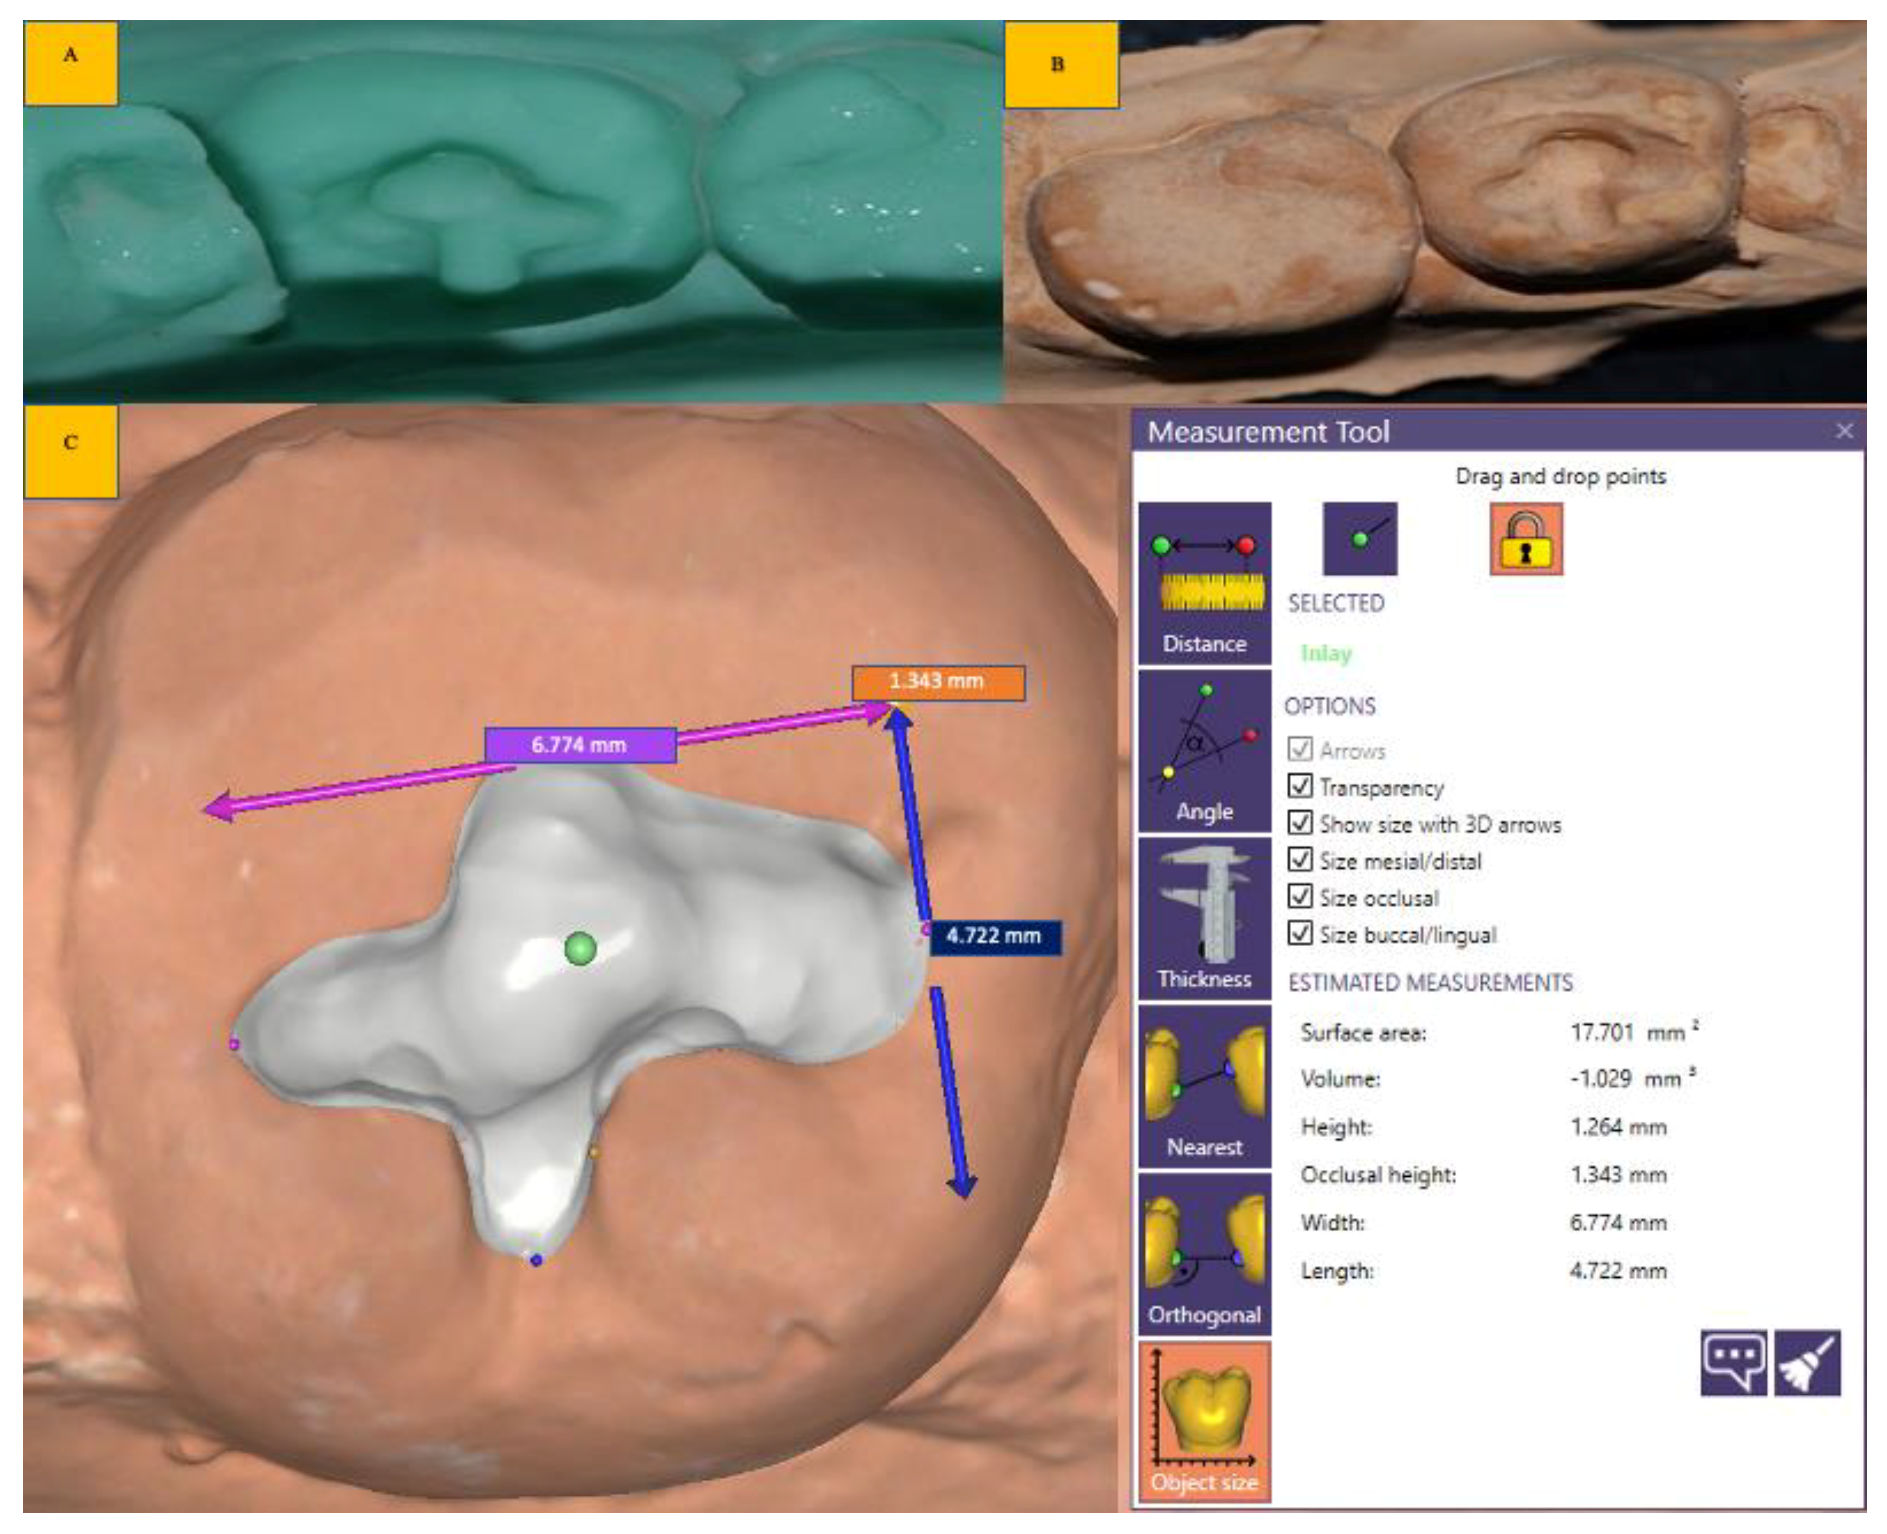

- Scanlan, C.A.; Rahmani, H.; Bowles, R.; Bennamoun, M. Three-Dimensional Scanning for Measurement of Bulk Density in Gravelly Soils. Soil Use Manag. 2018, 34, 380–387. [Google Scholar] [CrossRef]